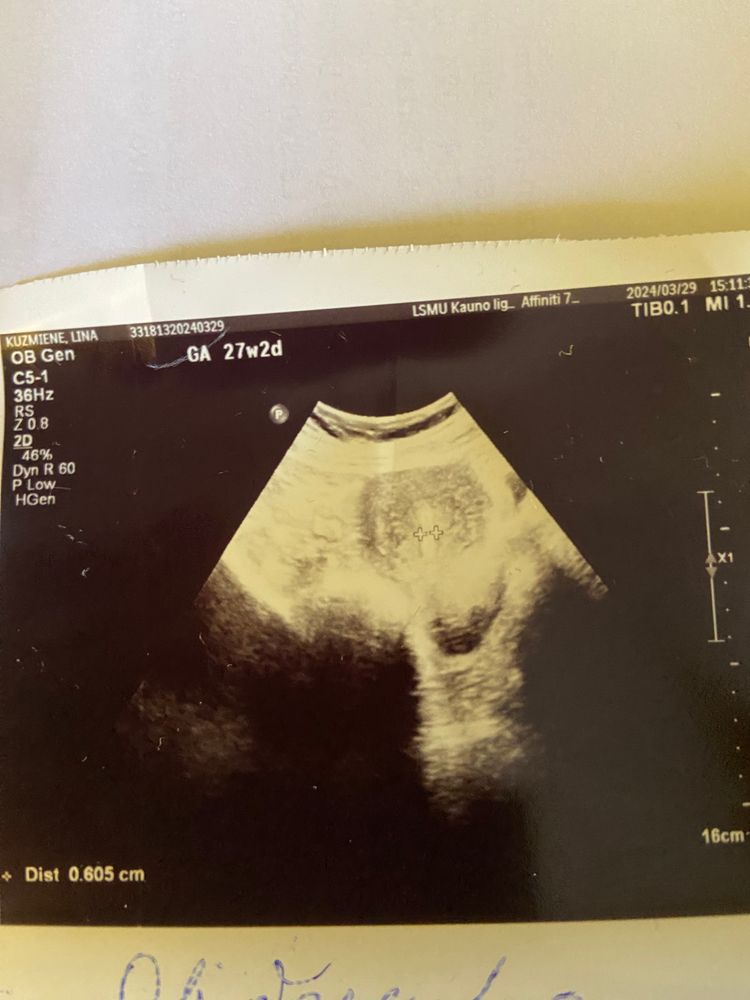

Kristina , мне в больнице вообще сказали, что ничего нет, сегодня был плановый осмотр у Г и это уже его узи. Тут на эти выходные пасха, сказал приходить во вторник, если не закончится кровотечение